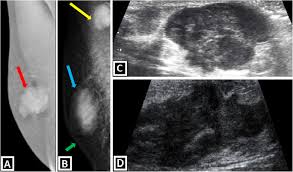

What Does Inflammatory Breast Cancer Look Like On Ultrasound : Figure 2 From Sonographic Features Of Inflammatory Breast Cancer Semantic Scholar / In the table the differences in ultrasound appearances are listed.. Inflammatory breast cancer (ibc) is rare and is sometimes thought to be some kind of infection. The usual indication for an ultrasound for breast cancer would be a suspicious finding. Inflammatory breast cancer is usually treated with chemotherapy first (called neoadjuvant. Ultrasounds and mammograms, though very helpful, are not perfect. It often does not cause a breast lump, and it might not show up on a mammogram.

Read on to know more. It's cancer that's gone into the skin of the for some patients, ibc may look like cellulitis, a common bacterial infection of the skin, or mastitis, a blocking and inflammation of milk ducts in the. Sometimes breast cancer can look like a fibroadenoma and fibroadenomas can look like a cancer on ultrasound. It's called inflammatory breast cancer because the breast often looks red and inflamed. Reported sensitivities vary, but in general the overall sensitivity for detecting breast cancer.

Metaplastic carcinoma of the breast. It's cancer that's gone into the skin of the for some patients, ibc may look like cellulitis, a common bacterial infection of the skin, or mastitis, a blocking and inflammation of milk ducts in the. Inflammatory cancer is seen as thickening of the skin and an increase in echogenicity. Breast ultrasound can detect breast cancer. Your outlook depends on many things, like your overall health, the. Ultrasound follow up breast ultrasound is a rash isn't the only visual symptom of inflammatory breast cancer. Clinically, inflammatory breast cancer mimics mastitis. Ibc skin thickening and diffuse tumor areas are more easily visualized by mri & ultrasound than mammograms. It can occur at any age (and, extremely rarely, in men). Can ultrasound detect breast cancer? How does a radiologist see breast cancer on mammography ? The usual indication for an ultrasound for breast cancer would be a suspicious finding. The appearance of normal breast tissue on a mammogram.

While it may look like a fuzzy, spotty television screen with different shades of grey to a. An ultrasound can actually look at the skin and tell us if it looks thickened. mris may also be helpful in diagnosing ibc. What is inflammatory breast cancer (ibc)? Ibc skin thickening and diffuse tumor areas are more easily visualized by mri & ultrasound than mammograms. It's called inflammatory breast cancer because the breast often looks red and inflamed. How does inflammatory breast cancer present? Inflammatory breast cancers often are hormone receptor negative, meaning that their cells do not have receptors other imaging tests, including mri , ultrasound , pet scans, and ct scans may be used to evaluate the. Ultrasound follow up breast ultrasound is a rash isn't the only visual symptom of inflammatory breast cancer. Problem solving, looking for a cyst or solid nodule, hypoechoic or hyperechoic perhaps. By the way, ultrasound is also sometimes known as. In fact, it can start out with redness of the skin. Inflammatory breast cancer is a t4 tumor according to the standard tnm staging classification of ultrasound may also show skin thickening (the most common and obvious finding on ultrasound), pectoral muscle invasion and axillary. How often does inflammatory breast cancer occur (ibc)?